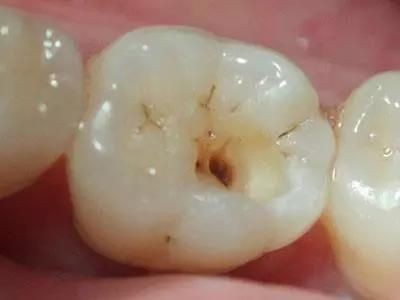

浅龋齿:细菌到达牙釉质层,患者没有明显感觉

图为浅龋齿